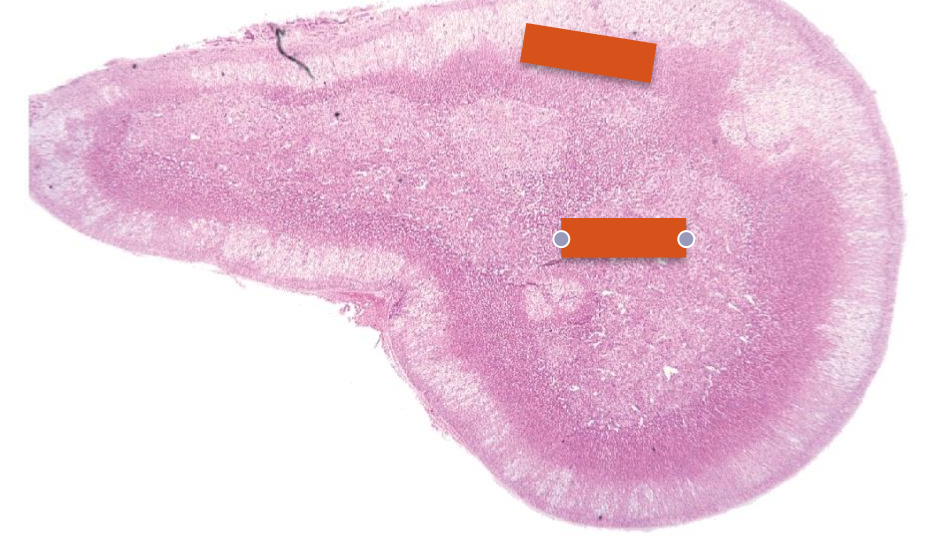

hypophysis (pituitary gland)

—red arrow= rathkes cleft

dark staining (blue)= adenohypophysis

light staining= neurohypophysis

neurohypophysis